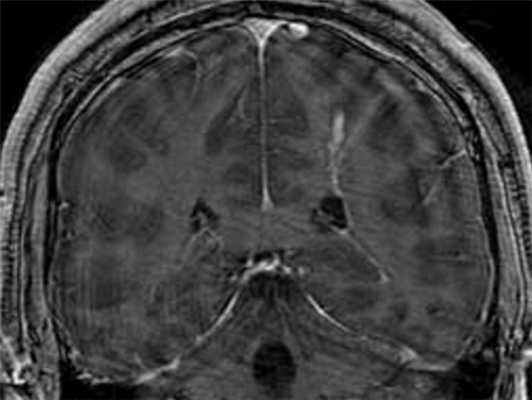

МРТ головного мозга. Т1-взвешенная МРТ с контрастированием. Венозный варикоз.

МРТ головного мозга. Т1-взвешенная МРТ с контрастированием. Венозная ангиома.